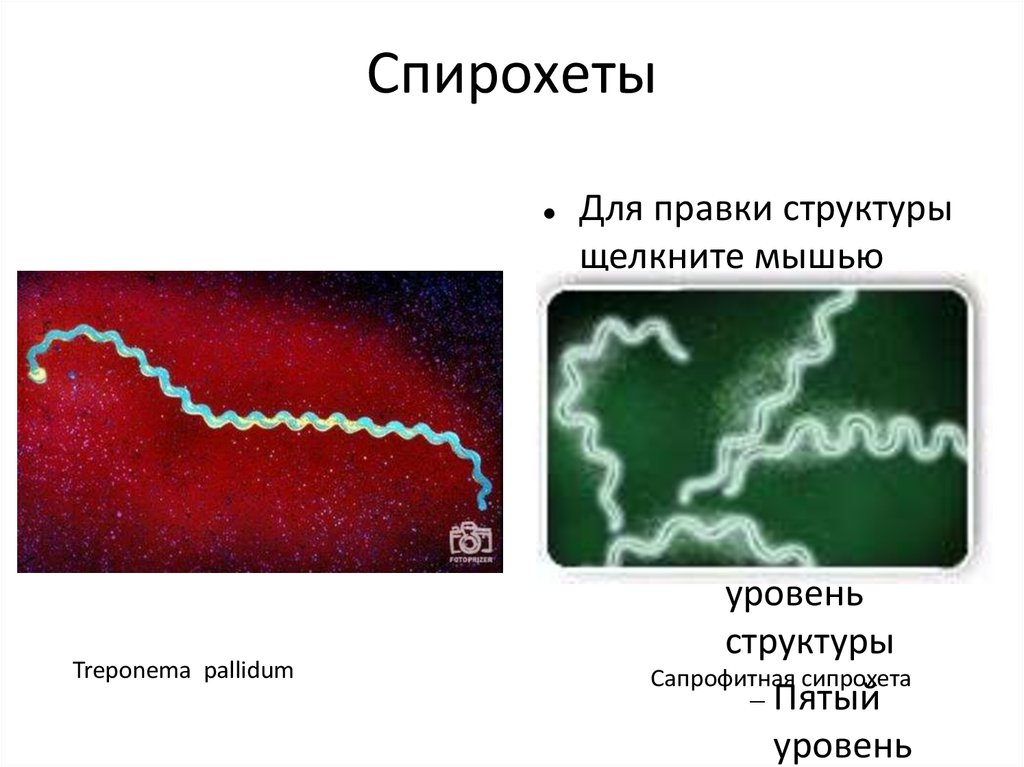

Лептоспиры: фотографии удивительных микроорганизмов